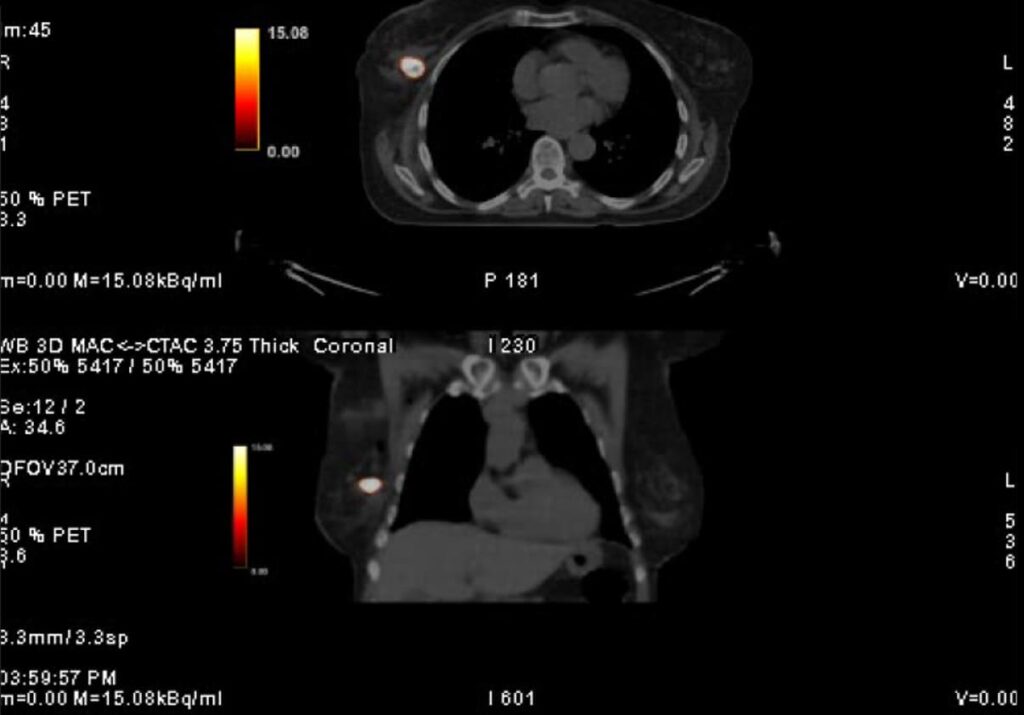

DCIS 7 days post injection PET Y90 scan

DCIS 7 days post injection

Human cases